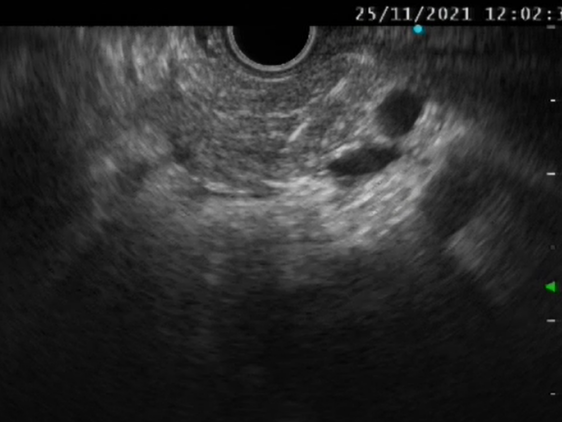

EUS—消化内镜领域的“第三只眼”

超声内镜(EUS)是将内镜和超声相结合的消化道检查技术,将微型高频超声探头安置在内镜顶端,当内镜插入体腔后,在内镜直接观察消化道黏膜病变的同时,可利用内镜下的超声行实时扫描,可以获得胃肠道的层次结构的组织学特征及周围邻近脏器的超声图像,从而进一步提高内镜和超声的诊断水平。